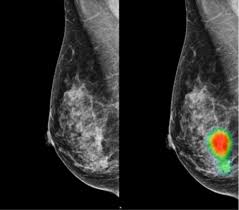

International Evaluation Of An Ai System For Breast Cancer Screening Nature from media.springernature.com Thermography is another option and can be an excellent source of very early detection for not only breast abnormalities, but other. If you have a condition like cancer, heart disease. Ct scans can detect bone and joint problems, like complex bone fractures and tumors. Your doctor might order ct scans to examine other parts of the body where breast cancer can spread, such as the lymph nodes, lungs, liver, brain, and/or spine. Also, during the examination, the diagnostician draws attention to the condition of the lymph nodes for the detection of metastases. But they can also cause cancer. Ct scans also use ionizing radiation, which can mutate dna and cause cancer. How does a ct scan (cat scan) work?

The proposed method is used to detect the cancerous cells. The lung cancer detection is the extension of the image processing that produces the results of feature extraction and feature selection after segmentation. Thermography is another option and can be an excellent source of very early detection for not only breast abnormalities, but other. Mammography, for example, detects possible breast tumours in women when such tumours are still too small to be found by physical examination of the detect cancer? This provides a series of images from many different angles.

The lifetime risk from typical ct scan exposure is small for older adults sue to the long time it takes cancer to develop. Ct scans can detect bone and joint problems, like complex bone fractures and tumors. Also, during the examination, the diagnostician draws attention to the condition of the lymph nodes for the detection of metastases. Each has its own strengths. Ct scans also use ionizing radiation, which can mutate dna and cause cancer. How does a ct or cat scan work? Detection of cancer prior to onset of symptoms (via several tests/imaging). This provides a series of images from many different angles. If cancer was detected through the nhs breast screening programme, you may need another mammogram or ultrasound scan. Bone scans, positron emission tomography (pet), and computed tomography (ct) all continue to be employed alone or in combination for the detection of breast cancers suspected to have spread. What does a ct scan show? Your healthcare provider will order a ct scan to help make a diagnosis of references. The whole appointment can take up to an hour and a half depending on which part of your body they are scanning.